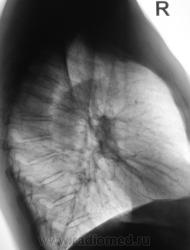

Я тоже сначала подумал о "периферическом", но похоже, "обломался". Сейчас добавлю боковые томограммы.

Сейчас добавлю томограммы в прямой проекции.

На томограммах не получили изображение округлой тени. Возможно, она имеет отношение к грудной стенке?

С Вашей точки зрения на боковх ТГ разве тень вне легочного поля? А что на срединных срезах справа паратрахеально?

Верхняя полая вена...да и эта тень медиальнее, чем та, с которой, вероятнее всего, работал автор случая...как мне кажется...

Если мне не изменяет память, в/полая вена так высоко "не забирается", образуясь от слияния плечеголовных вен чуть ниже уровня 1-го реберного хряща.